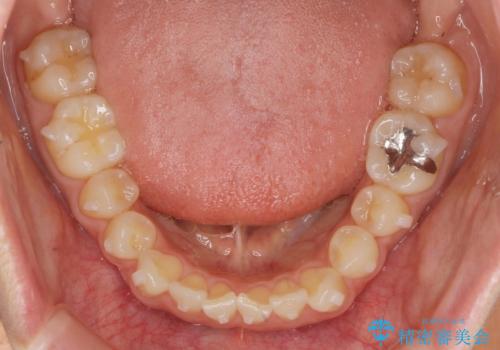

前歯の目立つガタつきをマウスピース矯正で治療

- 大きく傾いてしまった前歯のガタつきの改善を求めて来院されました。

前歯のガタつきをしっかりと取り、機能的・審美的に理想的な歯並びをマウスピース矯正で達成します。

強度のガタつきはマウスピース単体では並び切ることが難しいこともありますが、しっかりと装着していただいたことで良好な治療結果を得ることができました。